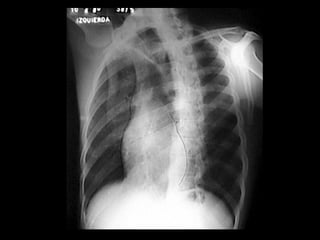

CRECIMIENTO DE LA AURÍCULA DERECHA Proyección PA Aumento de la prominencia del borde inferior derecho hacia el hemitórax derecho  Proyección OAI   Prominencia de la orejuela derecha inmediatamente por debajo de la aorta descendente.

CRECIMIENTO DE LAAURÍCULA DERECHA Proyección PA Aumento de la prominencia del borde inferior derecho hacia el hemitórax derecho Proyección OAI Prominencia de la orejuela derecha inmediatamente por debajo de la aorta descendente.